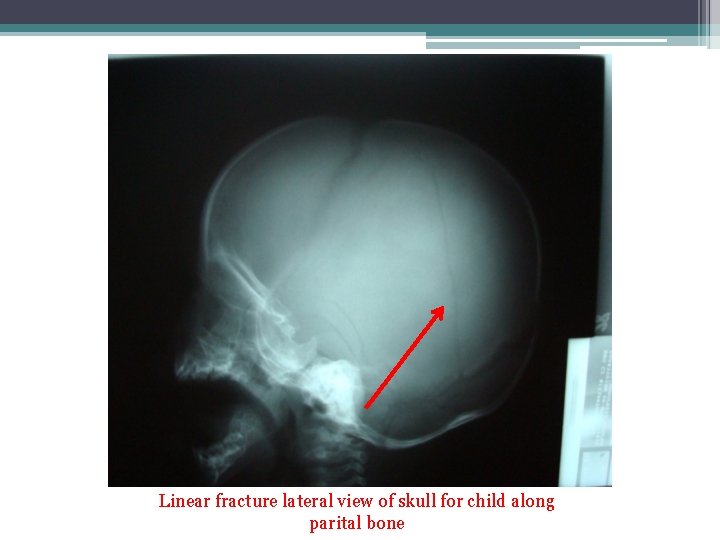

• Linear skull fractures: are breaks in the bone that transverse the full thickness of the skull from the outer to inner table.

Linear fracture lateral view of skull for child along parital bone